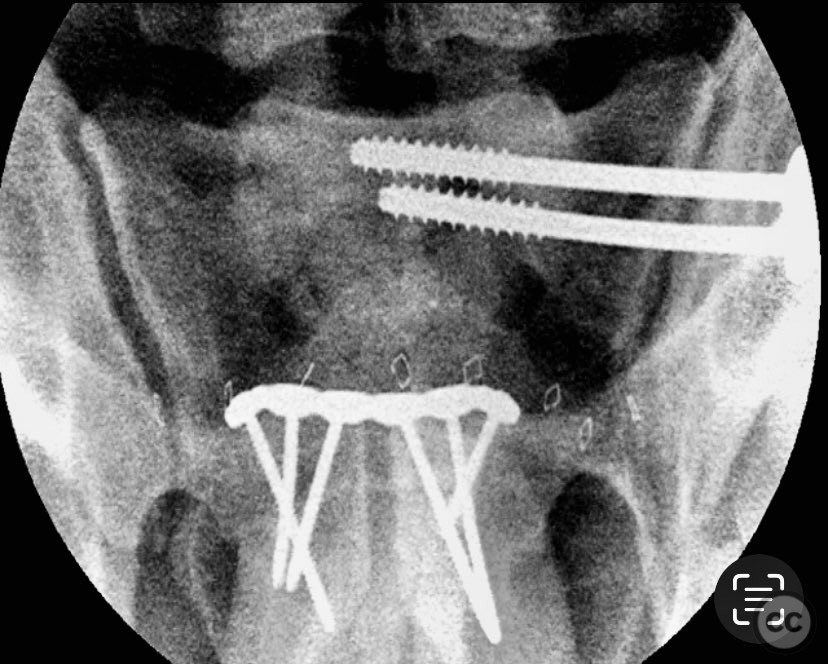

Clinical and radiological findings:  An adult patient sustained traumatic disruption of the symphysis pubis and an incomplete left sacroiliac (SI) joint injury. Initial radiographs and pelvic CT scan (performed without circumferential pelvic wrapping) demonstrated a widened symphysis pubis and an incomplete disruption of the left SI joint. The CT scan further provided information regarding bone quality, upper sacral morphology, patient body habitus, and vascular anatomy. No additional pelvic ring injuries were identified. AO/OTA classification: 61-B2.1 (lateral compression injury with incomplete posterior disruption).

Anatomical surgical approach:  A lower midline infraumbilical incision was made to expose the symphysis pubis. Subperiosteal dissection was performed to mobilize the rectus abdominis insertions and expose the pubic bodies. A pelvic reduction clamp was applied with tines docked in dense bone or soft tissue as dictated by local tissue quality, oriented to correct deformity while avoiding interference with planned plate placement. Following reduction, a contoured anterior symphyseal plate was applied and secured with cortical screws. Upon removal of the clamp, persistent SI joint malreduction was noted. Under fluoroscopic guidance, a percutaneous pathway was prepared for a cannulated iliosacral lag screw, traversing the posterior ilium into the upper sacral segment, ensuring safe passage relative to neurovascular structures.

The intraoperative course revealed that indirect reduction of the incomplete SI joint injury via anterior stabilization was insufficient, necessitating direct percutaneous fixation. A single cannulated iliosacral oblique lag screw was inserted under fluoroscopic control, achieving reduction, compression, and stabilization of the SI joint. Surgeon-specific technical consideration included avoidance of large-diameter drills for the posterior ilium due to limited bone stock (approximately 3 cm of ilium available for purchase), and the preference for an appropriately sized washer to optimize compression without risking iatrogenic fracture.

Orthopaedic implants used:   3.5 mm anterior symphyseal plate with cortical screws; 7.0 mm cannulated iliosacral lag screw with washer